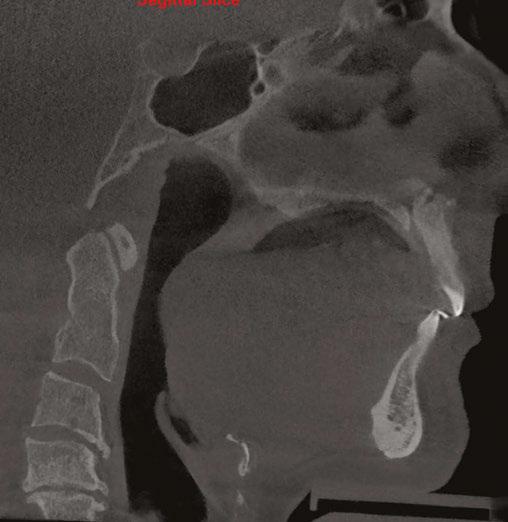

Figure 1 (left): A photo of a 69-year-old woman with a 2 mm anterior open bite and an excessive interlabial gap of 9 mm. Figure 2 (right): The sagittal slices of the above patient’s mandibular condyles reveal discontinuity of the cortical outline at the fossa and condyle (erosions). The altered condyles are flat along their path of function when she pushes her lower jaw forward to get the lips to touch in speaking, chewing, and breathing through her nose. Image captured using Dolphin® software (www.dolphinimaging.com)

Figure 3 (left): This same 69-year-old has undergone orthognathic surgery (bilateral sagittal split osteotomies and genioplasty) to close her open bite and shorten her anterior face height. This allows her lips to touch at rest and reduces energy usage to breathe, eat, and communicate. Figure 4 (right): The energy reduction at the mandibular condyles allows them to heal as evidenced by the recortication of the bone with the disappearance of the bony erosions. Image captured using Dolphin software (www.dolphinimaging.com)

12: A lateral cephalometric radiograph of a patient with excessive interlabial gap (radiograph was taken with lips postured closed). The excessive vertical has resulted in a long history of forward head posture as she pushes to close her lips. She has developed arthritis of the spine and spondylisthesis (AP vertebral instability) secondary to her consistent forward head posture. Image captured using Dolphin software (www.dolphinimaging.com)

Figure 17 (right): The lateral cephalometric radiograph, taken in repose, shows the extent of the interlabial gap, anterior open bite, and small airway. Note the silicone chin implant which was an attempt to ineffectively correct her severe skeletal discrepancy. Image captured using Dolphin software (www.dolphinimaging.com)